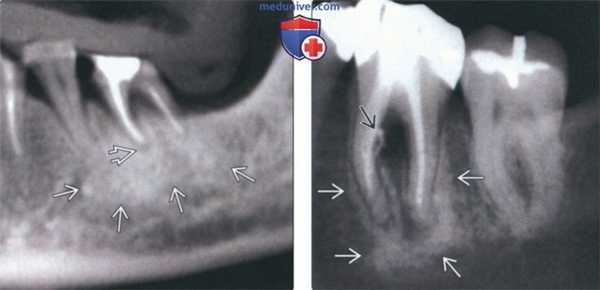

(Слева) На панорамной реформатированной КЛКТ определяется разрежение костной ткани возле периодонта зуба, подвергнутою эндодонтическому лечению, а также расширение периапикальною пространства ПДС с наличием широкой зоны склероза вокруг участка разрежения.

(Справа) На периапикальной рентгенограмме определяется склерозирующий остеит вокруг верхушечной и средней трети корней первого моляра нижней челюсти слева. В области фуркации определяется разрежение структуры костной ткани возле периодонта с выходом заполнителя вследствие перфорации мезиальною корня при неудачной попытке эндодонтическою лечения. (Слева) На профильном срезе (КЛКТ) визуализируется трансплантат, закрывающий дефект после удаления зуба. Некроз пульпы стал причиной выраженною склерозирующею остеита вокруг зуба. Склероз сохраняется даже после удаления зуба, достигая кортикальных пластинок нижней челюсти и распространяясь в канал НАН.

(Справа) На панорамной реформатированной КЛКТ определяется легкий периапикальный склероз вокруг расширенного пространства ПДС у вершины корня зуба. СО стороны зубов, подвергшихся эндодонтическому лечению, не должны обнаруживаться признаки воспаления до реставрации коронок.

(Справа) На периапикальной рентгенограмме определяется склерозирующий остеит вокруг верхушечной и средней трети корней первого моляра нижней челюсти слева. В области фуркации определяется разрежение структуры костной ткани возле периодонта с выходом заполнителя вследствие перфорации мезиальною корня при неудачной попытке эндодонтическою лечения.

(Слева) На профильном срезе (КЛКТ) визуализируется трансплантат, закрывающий дефект после удаления зуба. Некроз пульпы стал причиной выраженною склерозирующею остеита вокруг зуба. Склероз сохраняется даже после удаления зуба, достигая кортикальных пластинок нижней челюсти и распространяясь в канал НАН.